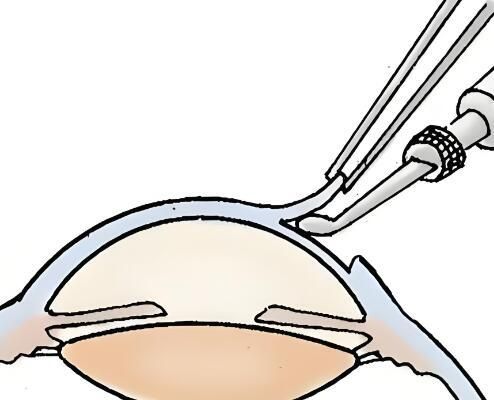

第四步:切割病变角膜

医生会在患者的眼部进行消毒和覆盖无菌布。然后,医生会使用角膜切割器或角膜缝线在病变的角膜上切割一个圆形开口。切割的大小和位置取决于病变的范围和需要。